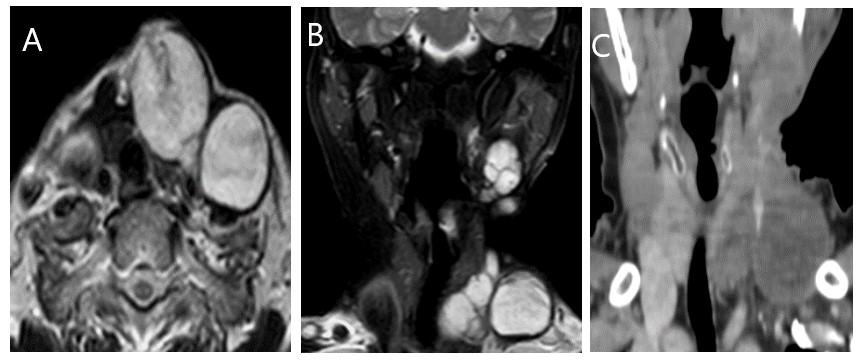

A comprehensive head and neck evaluation was conducted using magnetic resonance imaging (MRI), which revealed multiple variable-sized masses of mixed signal intensities on the left side of the neck. The involvement of the left submental and submandibular regions, masticator space, mandibular angle, posterior auricular area, posterior triangle, and carotid spaces were observed. These masses were inseparable from the left parotid tail. The presence of mixed SI on T1 and T2 WI was observed, indicating an underlying hemorrhagic component with heterogeneous enhancement on post-contrast imaging. The most substantial lesion was observed in the left posterior triangle, with dimensions measuring 3.7×4.7 centimeters. A few tiny reactive right submandibular and jugular nodes were detected (Figure 2(A,B)).

Computerized tomography (CT) revealed multiple heterogeneous enhancing soft tissue lesions involving left-sided neck spaces that were previously mentioned in the MRI report. The remaining findings of the study were deemed irrelevant with the exception of bilateral pulmonary nodules, with the largest measuring 10 millimeters (Figure 2(C)). This multicentric recurrent behavior raised an alert for the need for more radical resection and possible reconstructive procedure. A core needle biopsy was performed on one of the left-sided neck swellings, confirming the diagnosis of recurrent PMA.

Figure 2. MR and Post-Contrast CT Examination of the Patient Revealed: (A) Axial T2 Lobulated Lesion at the Left Supraclavicular Region with Hypointense Rim Wall Compressing Related Vessels Posteriorly. (B) Coronal SPAIR MR, Shows Multiple Lesions Seen at the Left Side of the Neck Submandibular and Left Supraclavicular Region. (C) Post-Contrast Coronal CT Show Mildly Enhancing Lesions at the Left Supraclavicular Region Encasing the Left Internal Jugular Vein.